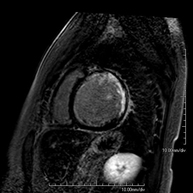

- Stress cardiac MRI

This non-invasive diagnostic test yields morphological and functional information about the heart and adjacent structures. These tests can be used to diagnose various congenital and acquired conditions. During the test, the technician will ask the patient to hold their breath several times for 10-15 seconds to obtain the clearest images possible. In the vast majority of cases, intravenous contrast (gadolinium) is required to complete the study. This type of contrast rarely causes adverse reactions. In addition, a drug (adenosine) is administered intravenously to exert an effect on the heart similar to that produced during physical exercise. The images obtained at rest and after pharmacological ‘stress’ are compared to detect deficits in blood supply to the left ventricle of the heart. The test lasts approximately 45–60 minutes. The patient must not consume any foods containing caffeine (coffee, tea, chocolate, cola drinks, etc.) 24 hours before the test. It is not recommended for patients with pacemakers. Patients should nevertheless inform the doctor if they have metal implants and/or surgical clips.